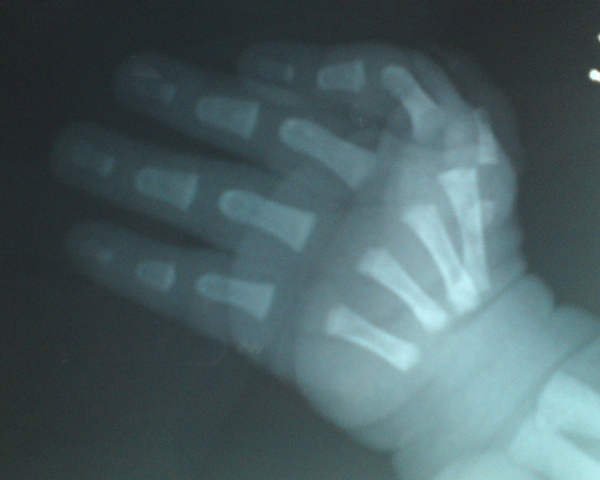

标题: PED3230:出生二天,发现拇指畸形。

出生二天,发现拇指畸形。

拇指掌指骨发育不良,食指有代替拇指趋势。

不是多指畸形是拇指畸形